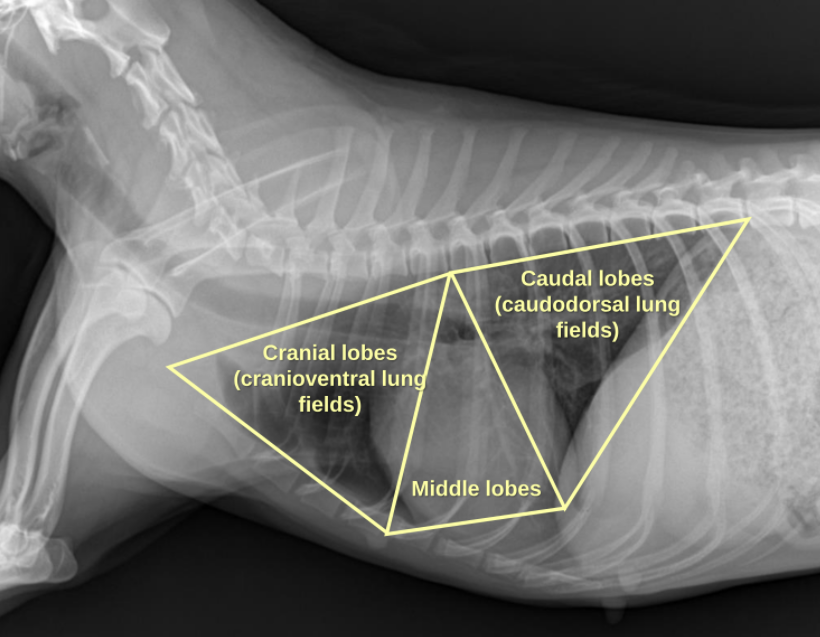

1. Normal Anatomy

| Thorax | |